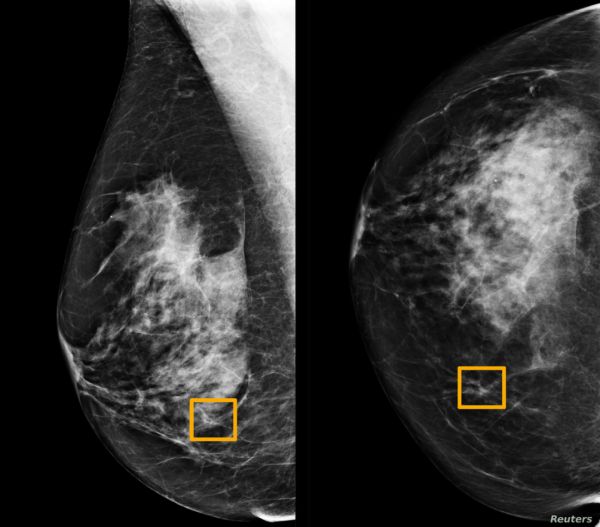

目前,超声等医学影像是乳腺癌筛查和诊断的主要手段,在乳腺癌的评估中起着至关重要的作用。但由于医疗资源等问题,全球约三分之二的人口仍无法获得放射学诊断信息。

乳腺癌常见的影像学诊断方法有乳腺摄影、超声、磁共振成像、核医学技术等,其中,超声检查的应用最为广泛,尤其在亚洲国家地区。与其他筛查技术相比,超声检查具有非电离辐射、无创性、高敏感性、便携性、可及性和成本等优势,当然,超声检查由于噪声和伪影的存在,其图像质量也往往较低。

在 SonoBreast 研究项目中,研究人员尝试应用机器学习技术对乳腺癌的超声图像进行分型。具体而言,研究人员创建了一个分类器模型,以一组乳腺癌变的超声图像为输入,输出给定图像的乳腺癌分子亚型的概率分布。

恶性预测 :该工具可预测乳房病变是恶性还是良性。对于患者病变的给定超声图像,提供病变的恶性诊断以及置信度(恶性概率)。

分子亚型 :该工具可预测乳癌性病变的分子亚型。对于患者病变的一组给定的超声图像(至少一个图像),将提供病变的预测分子亚型诊断以及置信度(每个亚型的概率)。

目前,研究团队已经发布了 web 应用程序,允许病人和医生使用该预测模型上传超声图像。用户可以上传一定数量的超声图像,然后根据需要选择超声筛查部分,在提交图像后,由模型计算预测结果,并用直方图显示模型图的置信度。